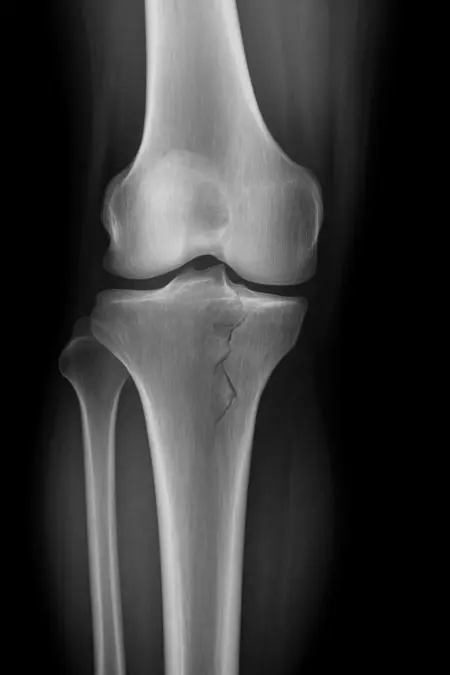

アートや写真の編集用に設計されたFlux Kontextのようなモデルを、医療画像、たとえば「単純な」骨折の赤色マーキングに使用できるか?

即答:面白い結果を出すが、過剰に反応し、医療ツールとしては信頼性に欠ける。これはアイデアを試すためのプロトタイプに過ぎない。

テスト結果:

- 偽陽性 ≈ 24%

- 骨折検出 ≈ 20%

感度モード(検出を優先、ノイズ多め)

- Euler、15ステップ、Karras

- Denoise:1.0

結果:

- 偽陽性 ≈ 80%

- 骨折検出 ≈ 86%

さらに攻撃的な設定(例:rk beta57、Denoise 1.0)では、**偽陽性100%、検出100%**という馬鹿げた結果に:すべてを赤で塗りつぶし、健常部もほぼすべて骨折と誤認する。未経験の目には区別がつかない。

Civitai用に作成した、100% AI生成の合成ミニデータセット(健康なX線10枚、骨折のあるX線10枚)でテスト:

- 健康な骨での偽陽性:100%

- 骨折検出:≈ 45%